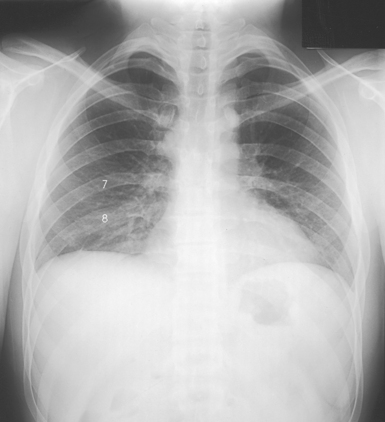

For certain conditions, such as pneumothorax and the presence of a foreign body, radiographs are sometimes made at the end of full inspiration and expiration (Figs. 10-29 to 10-31). Pneumothorax is shown more clearly on expiration because collapse of the lung is accentuated.

Fig. 10-30 Expiration in the same patient as in Fig. 10-29 (posterior rib numbers).